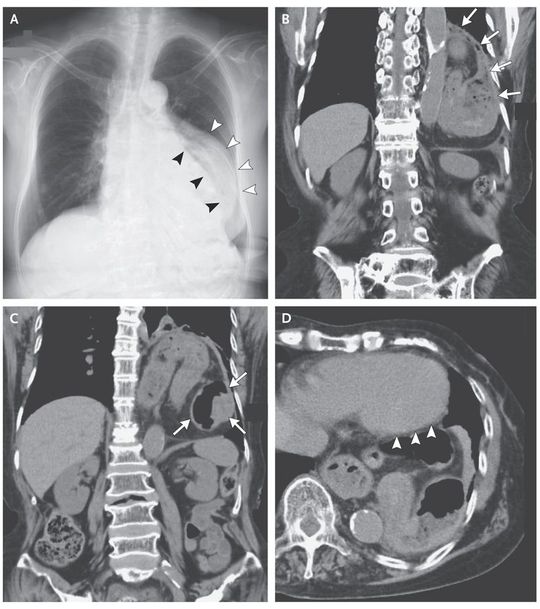

A 76-year-old woman with rheumatoid arthritis, diabetes mellitus, and hypertension presented with a 1-month history of palpitations that occurred only after she had eaten dinner. The sensation was felt at the center of the chest and lasted for 10 to 15 minutes after the meal. An electrocardiogram was unremarkable. A chest radiograph (Panel A) showed a mediastinal shadow (white arrowheads) lateral to the left heart border (black arrowheads). Computed tomography of the chest revealed a left diaphragmatic hernia (Panel B), with the stomach positioned in the thorax (Panel C, coronal view), abutting the left ventricle (Panel D, axial view, arrowheads). The stomach was visibly twisted, a finding consistent with a gastric volvulus. Gastric endoscopy revealed a volvulus, with twisting of the mucosa. After surgical repair of the hernia and volvulus, the palpitations resolved, and at follow-up more than 1 year after surgery, the patient remained free of symptoms.